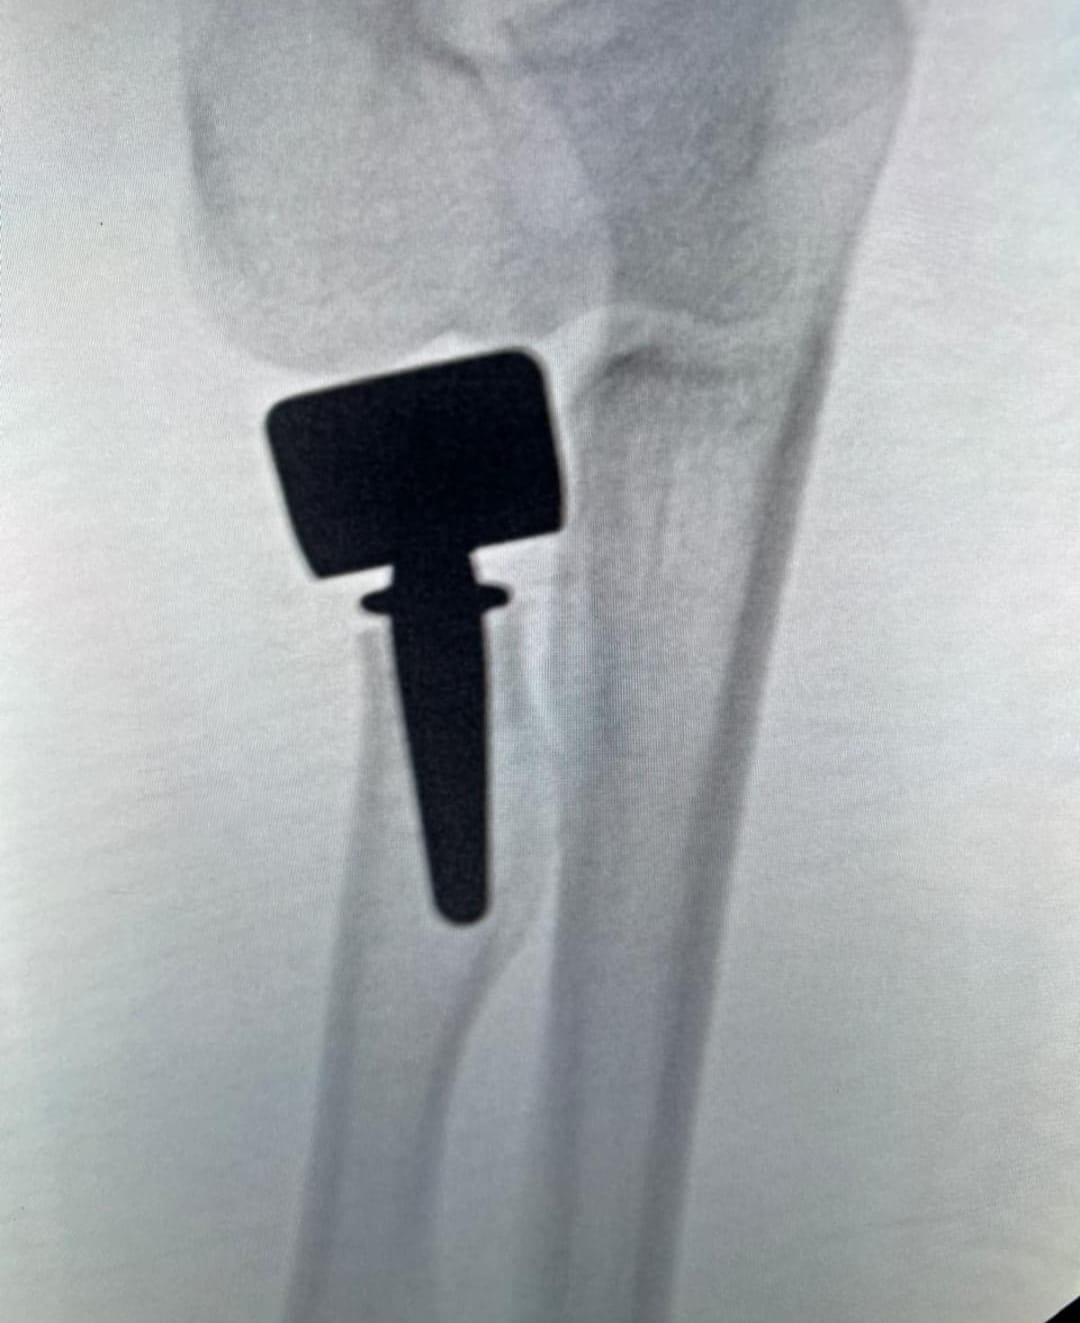

• Cirugía ortopédica reconstructiva

CASOS